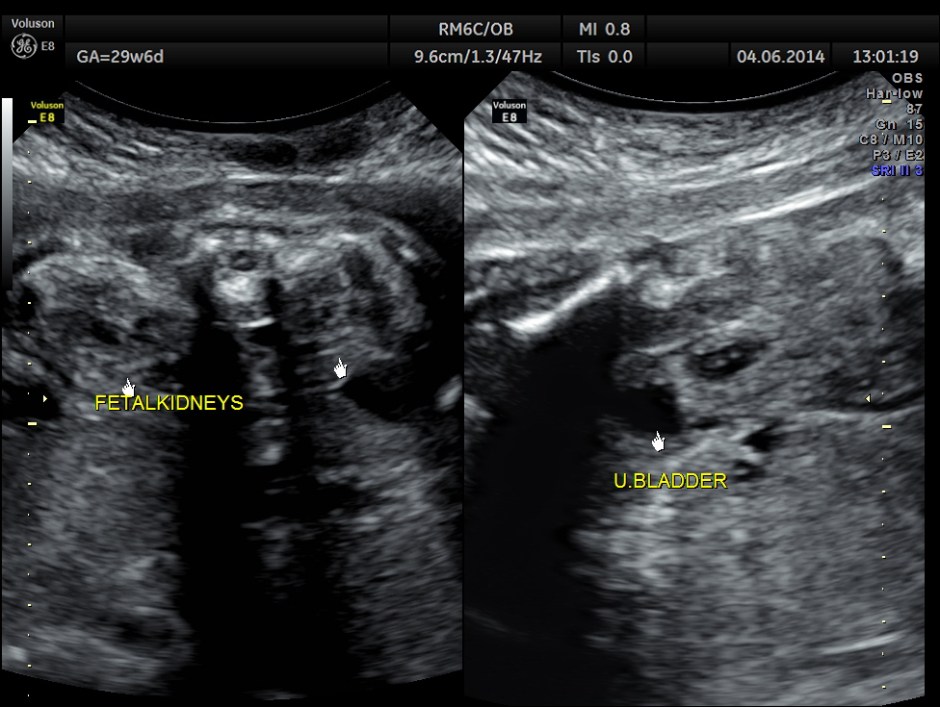

She came for a scan around 29 to 30 weeks of gestation . She had pregnancy induced hypertension detected 1 week ago .She had no history of hypertension during the earlier pregnancy , when the fetal loss had occurred after 3 months.

She had a thick placenta , but appears homogenous.

Biometric measurements show AC <2.3 %TILE

Umbilical artery P.I and R.I are high . The MCA / UMBILICAL arterial ratio is abnormal.

AFI appeared to be normal.

BPD , HC <10 % tile and AC is < 2.3 % tile .

AFI is normal .

But the doppler values are abnormal. Umbilical artery P.I. and R.I are > 95 % tile . MCA P.I. and R.I are lower .

The cerebroplacental ratio ( MCA/UA ratio ) is abnormally low -0.70 suggestive of utero placental insufficiency.